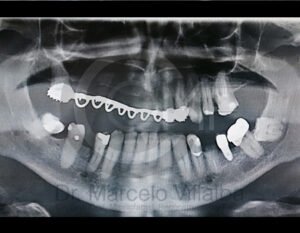

Antes de la extracción se realiza una valoración clínica y estudios de imagen, como radiografías panorámicas o tomografías, para conocer la posición del tercer molar, su relación con los nervios y planificar un procedimiento seguro y adecuado para cada paciente.

No es recomendable. Antes de extraer terceros molares es necesario realizar una valoración clínica y estudios de imagen para conocer la posición del diente, su relación con los nervios y el tipo de procedimiento más seguro para cada paciente.